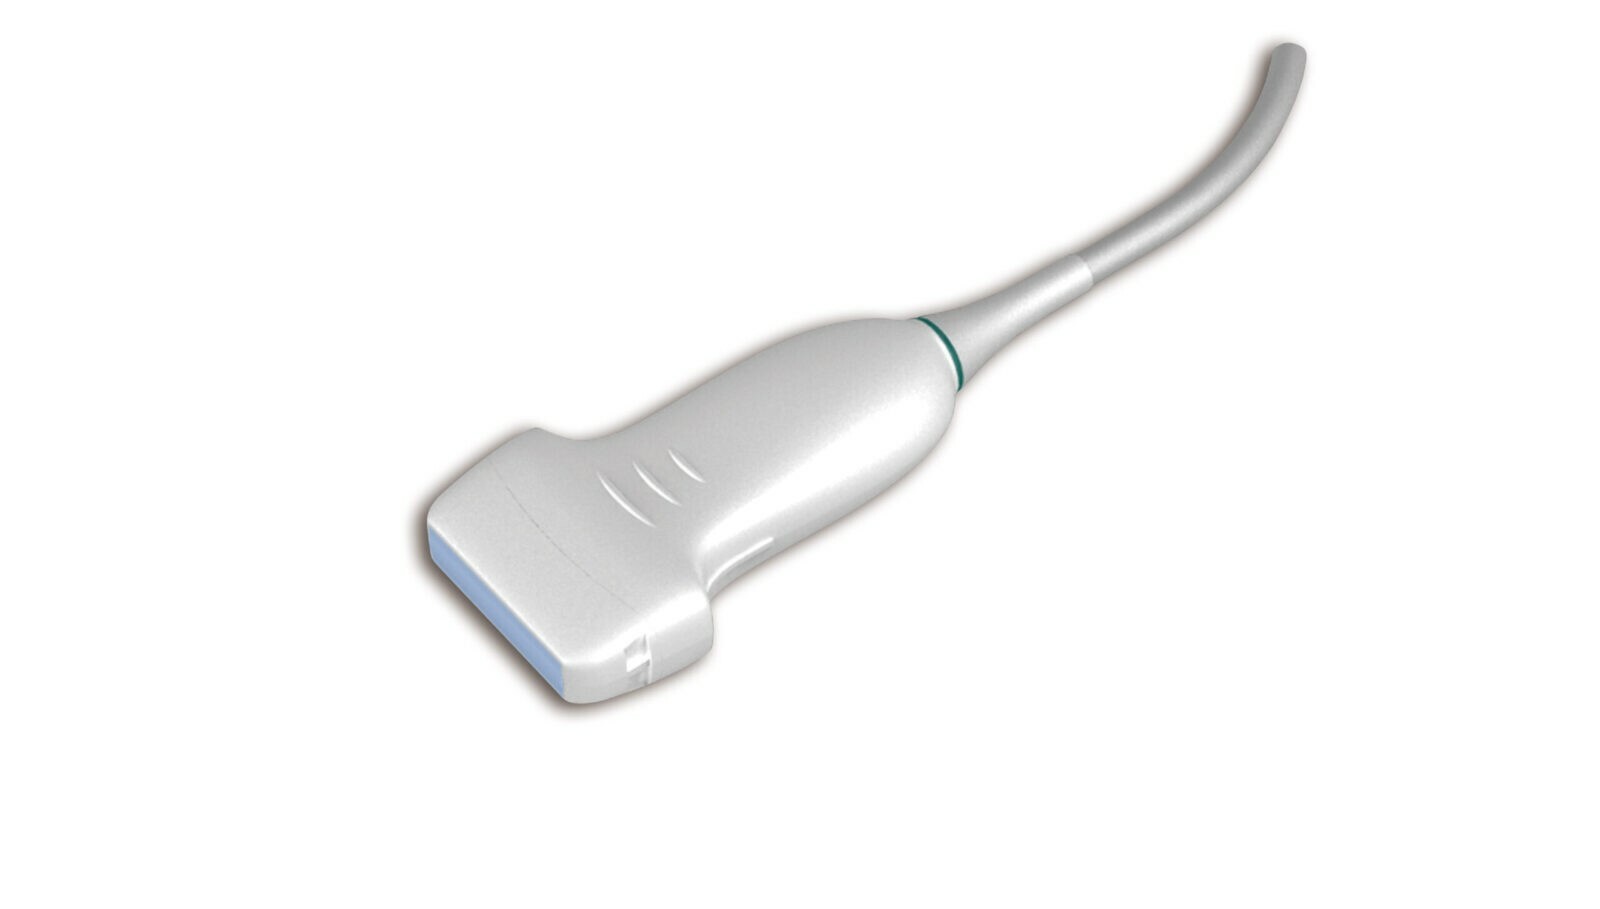

Конвексный C5-2Q

Линейный L12-5Q

Конвексный C5-2Q

Линейный L12-5Q

Объемный C5-2MD

Микроконвексный MC8-4D

Конвексный C5-2B

Линейный L742UB